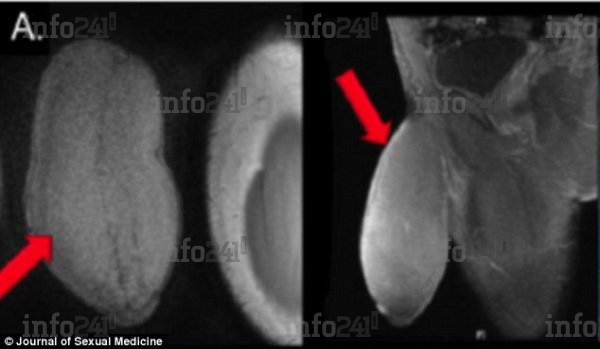

L’opération a été effectuée à la demande du jeune homme dont le membre mesurait près de 18 cm de long au repos, avec une circonférence de 25 cm, ce qui lui donnait l’apparence d’un « ballon de football américain » selon les chirurgiens qui l’ont examiné. Un format hors norme qui l’empêchait d’avoir des rapports sexuels et de pratiquer certains sports. En outre, l’adolescent souffrait également de priapisme, un trouble qui provoque des érections involontaires.

Ses organes génitaux aux rayons X